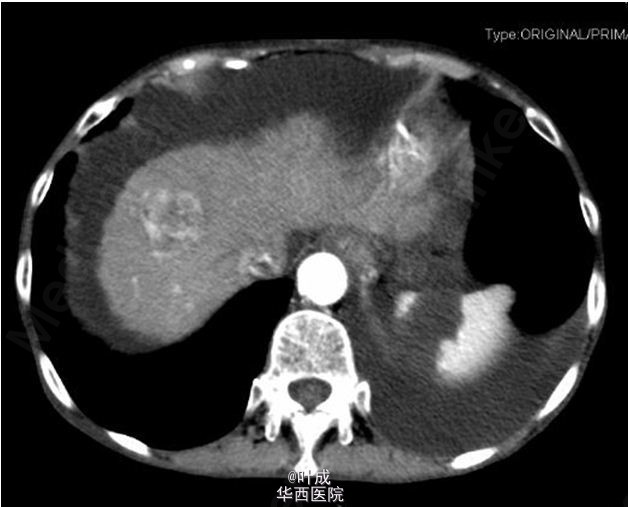

查体:T:37.2℃,P:98次/分,R:18次/分,BP:155/84mmHg,心肺查体无特殊,腹部膨隆,全腹软,上腹部轻压痛,无反跳痛,腹部未触及包块,肝肋下1-2cm,剑下5cm,质地较硬,脾脏肋下未触及,双下肢轻度水肿。 辅助检查:血常规:Hb 96 g/L,WBC 3.86 10^9/L,N 75.3 %;肝肾功:TB 18.0 umol/L,DB 10.7 umol/L,ALT 33 IU/L,AST 109 IU/L,ALB 25.6 g/L,ALP 142 IU/L,GGT 175 IU/L,肾功未见异常;AFP 214.50 ng/ml,CEA 4.23 ng/ml,CA19-9 89.39 U/ml,CA-125 478.40 U/ml;输血前检查:乙肝表面抗体、乙肝e抗体、乙肝核心抗体阳性,余阴性,高精度HBV病毒载量 阳性,<20 IU/mL;凝血常规、大小便常规未见异常;腹水常规示黄色微混,有核细胞 20 10^6/L,总蛋白 12.6 g/L。腹部增强CT:肝硬化,腹水,食管-胃底粘膜下、胃周静脉曲张,脾大;右半结肠肿胀,肝门区、肠系膜根部及腹主动脉周围淋巴结增多,部分增大,自发性腹膜炎?与旧片比较腹水明显增多,淋巴结明显增多。肝右前叶上段片团影,肝右前叶上段见一大小约2.8×2.8cm的稍低密度影,其内见稍高密度影,边界模糊,增强扫描呈不均匀强化(图1-3)。